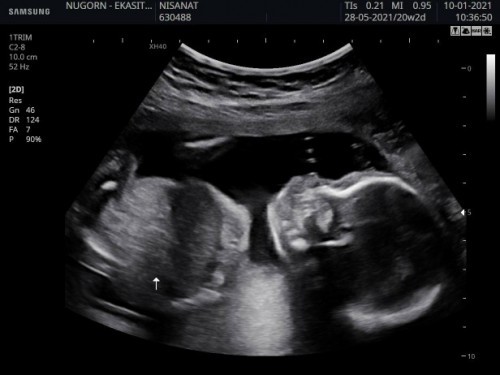

อายุครรภ์13สัปดาห์ค่ะ แต่เด็กเป็นตัวชัดเจนมาก มีแม่ๆคนไหนซาวต์แล้วชัดแบบนี้บ้างค่ะ

ตอน 13w2 ค่ะ เปิดภาพมา โบกมือโชว์ 5 นิ้ว แถมดุ้กดิ้กเล่นไปมา😆